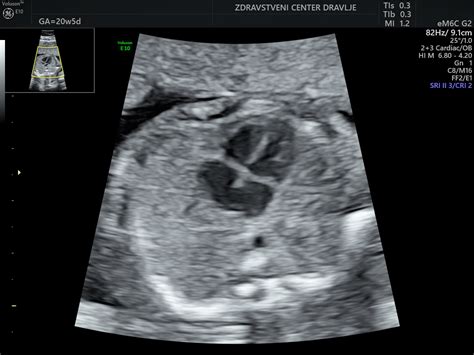

V 25. tednu nosečnosti otrok od temena do trtice meri približno 22 cm in tehta okoli 700 gramov. Njegova koordinacija se izboljšuje, kar mu omogoča, da lahko zdaj stisne pest ali z rokami seže proti stopalom. Zaradi vedno boljše prekrvavitve začne otrokova koža dobivati rožnato barvo, saj se pod njo oblikujejo kapilare, ki se polnijo s krvjo. Pljuča se aktivno pripravljajo na prvi vdih in nadaljujejo s proizvodnjo surfaktanta, snovi, ki bo po rojstvu ključna za normalno delovanje pljučnih mešičkov. Hkrati se razvijajo tudi živci okoli otrokovih ust, kar je pomembno za sesalne reflekse.